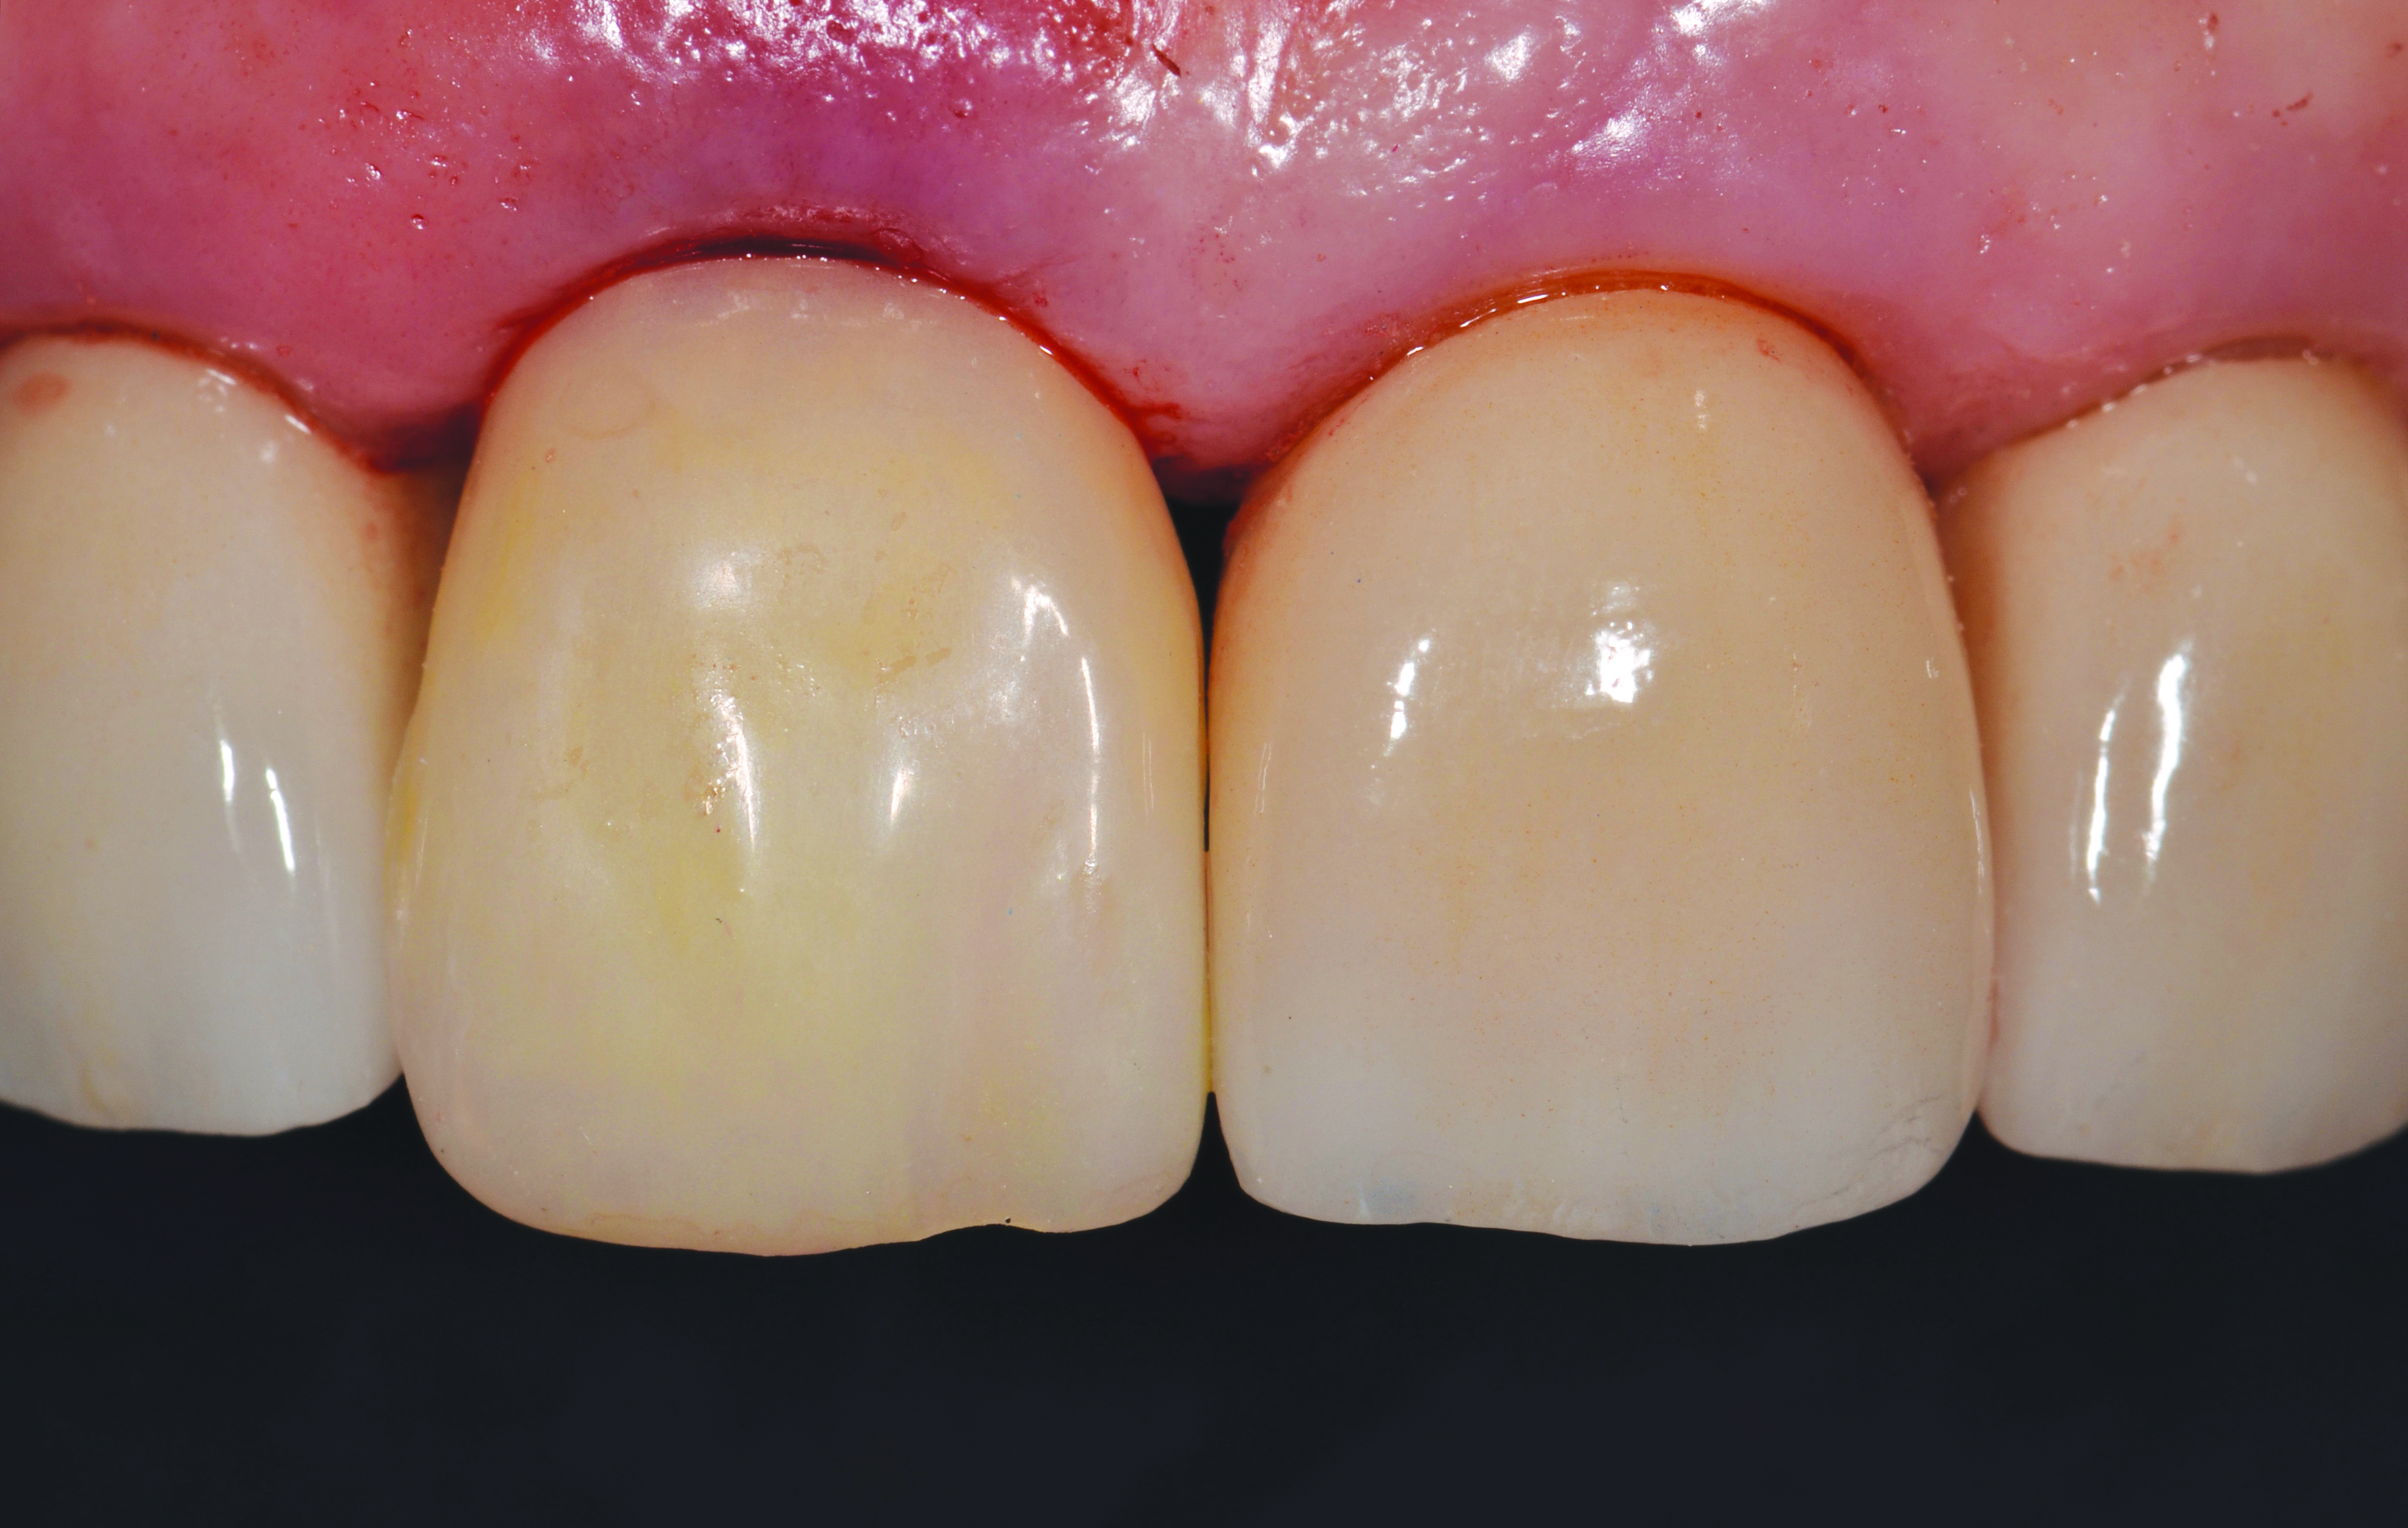

A 62-year-old woman presented on emergency, reporting having fractured her right central incisor (Figure 1). The area was asymptomatic and demonstrated no problems other than the embarrassment associated with the loss of her front tooth. Diagnostic records were made and an Essix retainer (essix.com) was fabricated to help alleviate her immediate esthetic concerns. Due to the lack of tooth structure incisal to the gingiva, the prognosis of the tooth was very guarded. Various options to restore this area were presented to the patient, leading to her ultimate choice of a dental implant. A diagnostic CBCT scan of the patient was attained and the patient left the office wearing the retainer.

Fig 1. Pre-operative situation of a fractured tooth No. 8.

Figure 1